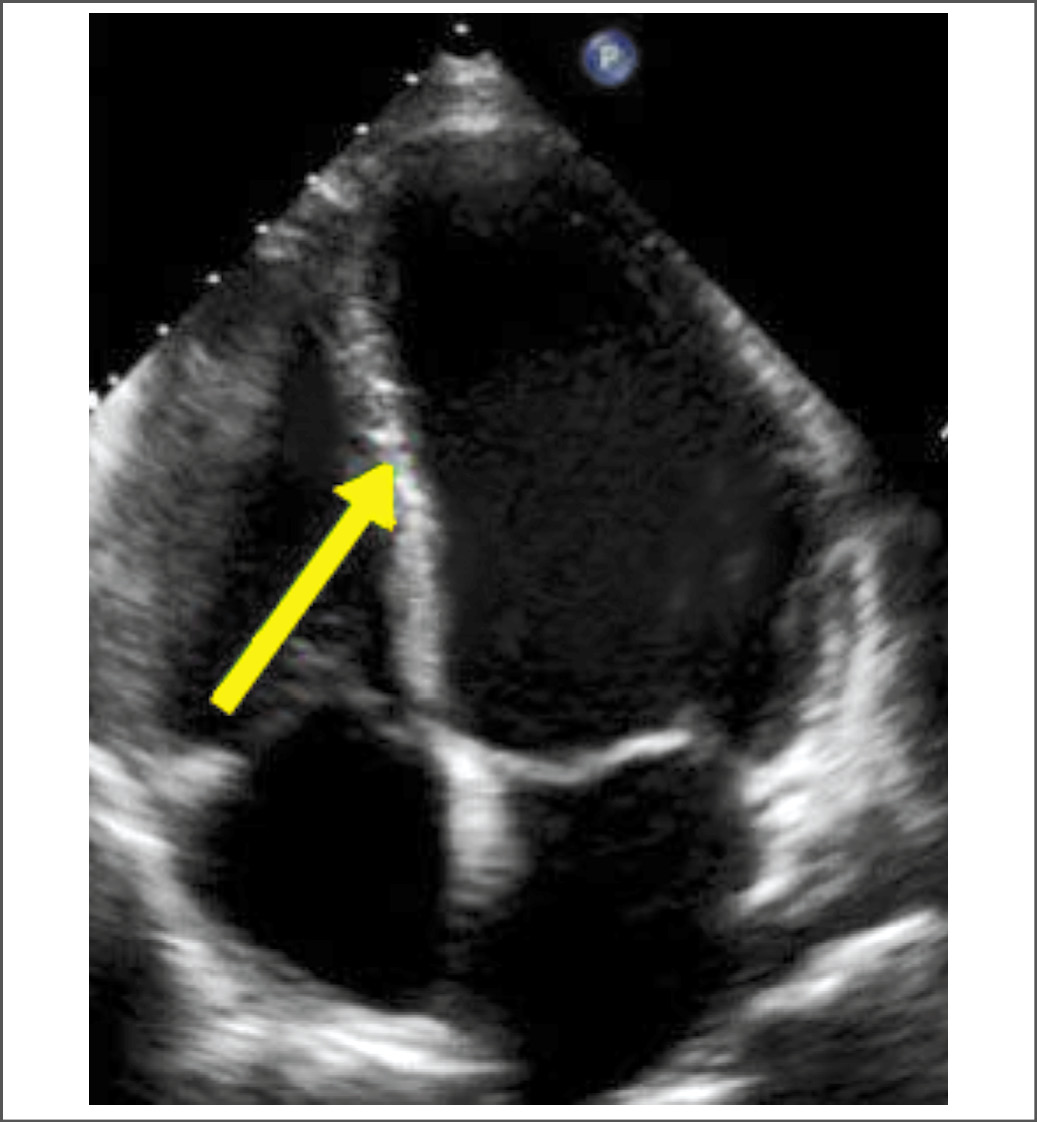

Спустя 6 ч после поступления в связи с сохраняющимся дискомфортом в грудной клетке и повышенным содержанием тропонина выполнена коронарография: коронарные артерии без гемодинамически значимых стенозов. По данным ЭхоКГ: ФВ ЛЖ – 55%, ЛЖ не увеличен (конечно-диастолический размер – 45 мм, конечно-систолический размер – 32 мм, КДО – 90 мл, КСО – 45 мл), МЖП – 8,0 мм, задняя стенка ЛЖ – 7,0 мм; выявлены нарушения локальной сократимости ЛЖ – выраженная гипокинезия базальных, заднеперегородочного и нижнего сегментов, боковой стенки ЛЖ на срединном и базальном уровнях; правые отделы сердца и клапанный аппарат без особенностей; расхождение листков перикарда за задней стенкой ЛЖ 4–5 мм, за боковой стенкой ЛЖ и правого предсердия – 10–12 мм; присутствует жидкость в плевральных синусах (рис. 2).

Рис. 2. ЭхоКГ пациентки М. при поступлении. Отсутствует утолщение стенок ЛЖ (стрелка указывает на МЖП).

Fig. 2. Patient M. EoCG on admittance. There is no thickening of the walls of the left ventricle (arrow indicates an interventricular septum).

Традиционно считается, что амилоидоз сердца приводит к утолщению стенок миокарда как ЛЖ, так и правого желудочка и нарушению их наполнения – так называемым рестриктивным изменениям [3, 6]. Согласно данным, опубликованным A. Martinez-Naharro и соавт., при выполнении магнитно-резонансной томографии и сцинтиграфии сердца больным с амилоидозом гипертрофия ЛЖ (ГЛЖ) выявляется у 82% пациентов с AL-амилоидозом и у 97% пациентов с транстиретиновым амилоидозом [6]. Как известно, по предложенным экспертами алгоритмам диагностики кардиального амилоидоза начинать дифференциальную диагностику предлагается именно с оценки толщины стенок миокарда, условно обозначаемой как «ГЛЖ», и рестриктивного типа наполнения ЛЖ [3, 7, 8]. В нашем случае согласно результатам повторных ЭхоКГ у пациентки отсутствовали признаки ГЛЖ и гипертрофии правого желудочка, а также проявления рестриктивной кардиомиопатии и низкого вольтажа комплексов ЭКГ, что характерно для амилоидоза сердца. Именно все эти обстоятельства позволили нам исключить диагноз амилоидоза, при том, что наша клиника имеет достаточно большой опыт диагностики этого заболевания [9–11].